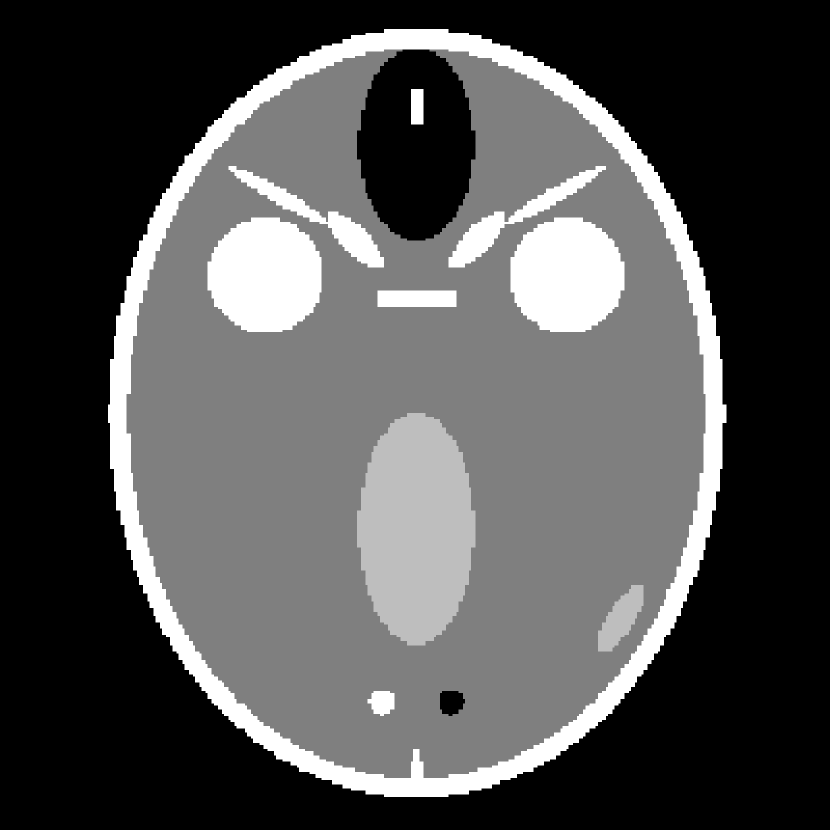

For the present study, we employ the breast phantom originally described in [42] and displayed in Fig. 4. It consists of pixels within the circular image region, contained in a array. The breast phantom has a small region of interest (ROI) containing 5 tiny ellipses which model microcalcifications. The gray values range from 1.0 to 2.3. The modeled tissues and corresponding gray values are fat at 1.0, fibroglandular tissue at 1.10, skin at 1.15, and microcalcifications ranging from 1.9 to 2.3. The sparsity in the gradient magnitude image is , or roughly one fifth of . Because we are investigating the utility of gradient-magnitude sparsity-exploiting algorithms, it is important that the test phantom have a realistic sparsity level relative to the actual application.

The breast phantom study is repeated employing a variation of the FORBILD head phantom [46] which is highly sparse in the gradient-magnitude image. The present version of the phantom, which is seen in Fig. 11, does not have the ear objects of the original phantom, and the contrast levels have been increased so that the minimum gray-level contrast is the same as for the breast phantom. The gradient magnitude sparsity is , or approximately a quarter of the breast phantom. In Fig. 11, the obtained for -magnitude, -roughness and -TV are shown as function of with and .